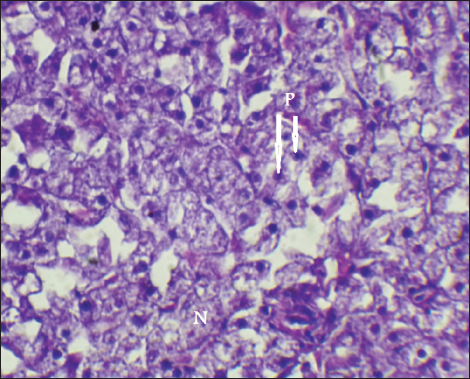

The result of histopathological alteration of the liver revealed degenerative and necrotic changes in liver tissue distinguished by pyknosis with the existence of necrosis in cells (Figs. 14 and 15) also, the result revealed dilation of the sinusoids with cytoplasmic vacuolation (Fig. 16).

Fig. 14. Histopathological sections of liver of C. carpio showing necrosis(N) and Pyknosis (P) (H&E X40).

This study showed that C. carpio contains different concentrations of the selected heavy metals in the liver, gill, and muscle, the causes of this differences is due to the collection of samples at different intervals and, therefore, the level of contamination in water and food and sediment varies depending on the time period also differences in fish’s internal uptake and water temperature. Kalay et al. (1999) revealed that the amounts of minerals that different fish species accumulate in their tissues vary noticeably. Furthermore, Canli and Atli (2003) revealed that heavy metals levels in fish vary between species and different aquatic environments. Conversely, Farkas et al. (2000) linked variations in mineral concentrations among fish to their feeding habits, the ability of each species to bioconcentrate, and the mineral’s biochemical characteristics. Roméo et al. (1999) also state that the environment, metabolism, needs, level of contamination in water, sediment, and food, as well as water temperature and salinity, all affect a fish’s ability to accumulate heavy metals. Also, Brraich and Kaur (2017) revealed that the levels of heavy metals in different fish organs are directly impacted by the contaminating of the aquatic environment and by the fish’s internal uptake, control, and removal of heavy metals.

Fig. 15. Histopathological sections of liver of C. carpio showing necrosis (N) (H&E X40).